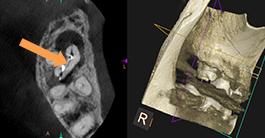

下の奥歯の違和感よ腫脹を主訴に来院。下顎大臼歯の根管内の感染物質を除去した後、徹底的に洗浄消毒を行い、炎症症状の消失となった。

矢印の先に金属片状の不透過象が認められる。根尖に感染炎症による透過像を認める。

矢印の先に金属片状の不透過象が認められる。根尖に感染炎症による透過像を認める。

根管内の感染源と共に除去された。

根管内の感染源と共に除去された。

根管治療終了後。炎症症状は無くなり、骨の回復も認められる。

根管治療終了後。炎症症状は無くなり、骨の回復も認められる。